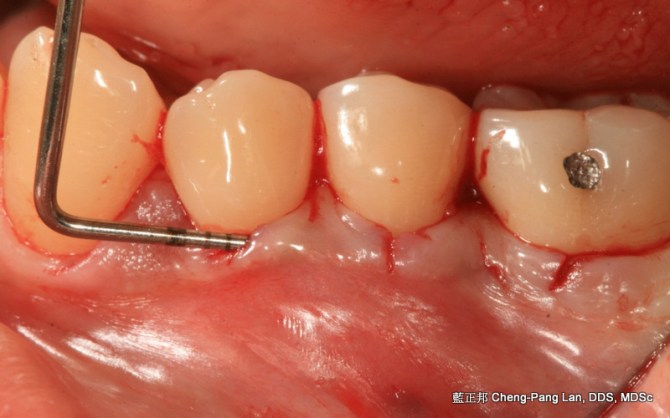

Root Coverage – Tunnel Technique with Connective Tissue Graft – Case C Posted on September 28, 2013 by drlan 藍正邦 Cheng-Pang Lan, DDS, MDSc Share this: Share on Facebook (Opens in new window) Facebook More Email a link to a friend (Opens in new window) Email Share on X (Opens in new window) X Share on Pinterest (Opens in new window) Pinterest Share on Tumblr (Opens in new window) Tumblr Like Loading...